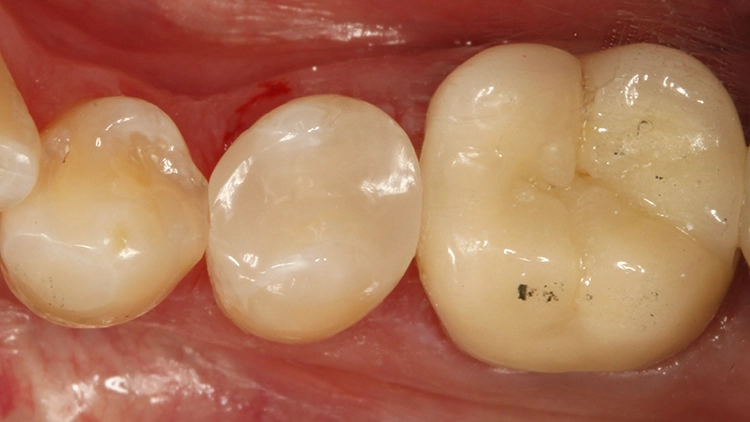

Der 55-jährige Patient störte sich an dem Randausbruch seines erst 10 Jahre alten Keramikinlays an Zahn 45 (Abb. 7). Er wünschte eine Neuversorgung mit Keramik. Nach eingehender Aufklärung und Beratung konnte er davon überzeugt werden, dass in der Dimension der Kavität eine direkte Kompositversorgung genauso funktionieren könnte.

Der sehr anspruchsvolle Patient haderte zunächst wegen der Ästhetik von „Kunststofffüllungen“: Er war der Überzeugung, dass hier keine adäquate Farbanpassung möglich sei, ließ sich aber auf den Vorschlag der direkten Kompositversorgung ein. Dieser Fall sollte dann eine Challenge für die Universalfarbe Venus Diamond One werden – aufgrund vorangegangener guter Erfahrungen von über 1,5 Jahren mit dem Material [10] konnte man sich ziemlich sicher sein, dass hier automatisch eine adäquate Farbanpassung stattfinden wird und gar keine hochspezifische individuelle Zahnfarbbestimmung erforderlich ist.

Die weitere Versorgung der Kavität erfolgte analog zu Fall 1 nach Anwendung eines klassischen Etch&Rinse-Mehrflaschenadhäsivs und schichtweiser Applikation und Polymerisation von Venus Diamond ONE (Kulzer) mit einem Hochleistungs-LED-Polymerisationsgerät > 1.000 mW/cm2 für jeweils 20 Sekunden Lediglich anstelle des Venus Diamond Flow Baseliners kam aufgrund der sehr hohen ästhetischen Ansprüche des Patienten Venus Diamond Flow in der Farbe A2 zum Einsatz – der Patient hätte keinen weiß-opaken Rand an seiner Restauration akzeptiert. Das Ergebnis (Abb. 9) überzeugte den Patienten nicht nur funktionell, sondern vorrangig ästhetisch: Auch hier passt sich die Universalfarbe perfekt an die Zahnhartsubstanz an. Zur Überprüfung der Ausdehnung der Überkappung wurde im Anschluss an die Versorgung eine Zahnfilm-Röntgenaufnahme erstellt (Abb. 10).